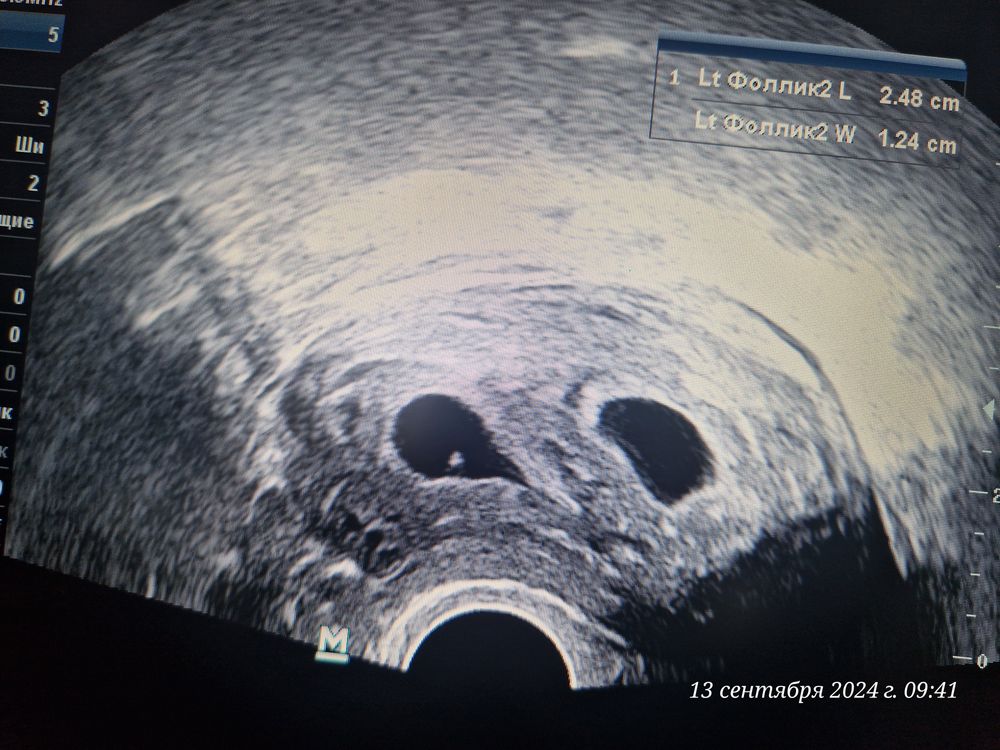

21 дпп. 5н 3д. Оба два 😍

Беременность✏️21 дпп - 13.09.24 Ну вот и состоялось первое наше УЗИ, уже такие большие бусинки😍 Не знаю зачем, но вчера сдала ХГЧ, просто так наверное или просто убедиться, что оба со мной🙏🏻 Результат оказался 37 303 МЕ/л не ожидала такой увидеть.

Диаметр первого ПЯ - 14 мм. ЖМ - 3,5 мм. Хорион до 4,8 мм

Диаметр второго ПЯ - 13 мм. ЖМ - 3.5 мм. Хорион до З,6 мм